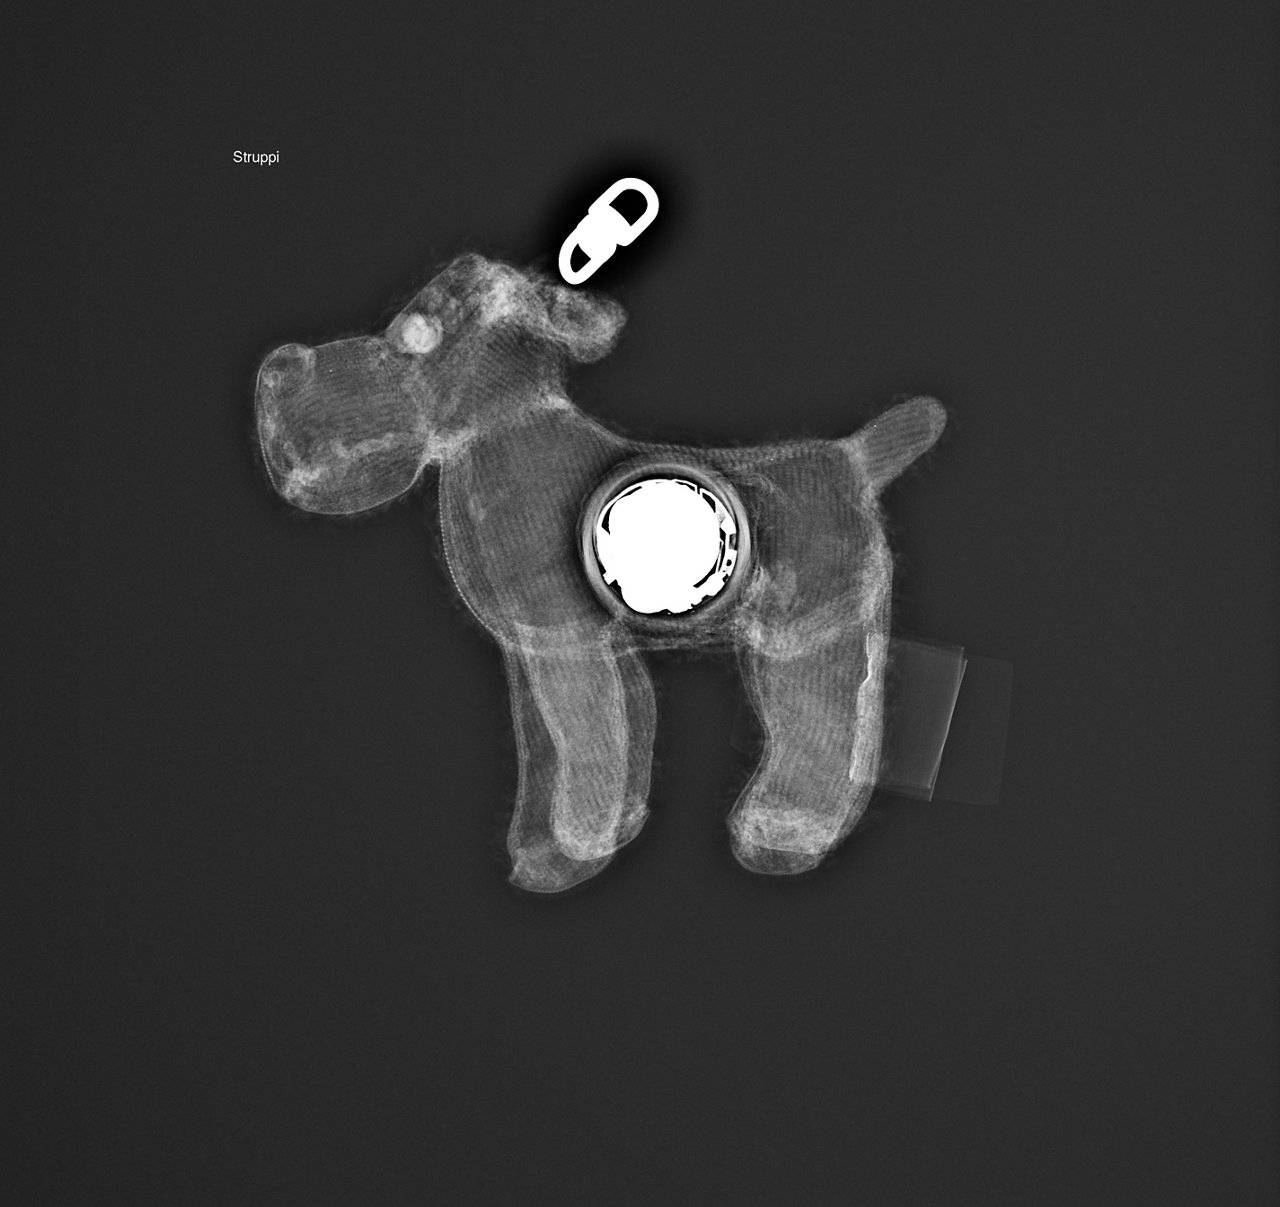

Teddy hängt am Infusionsständer in der Kinderonkologie